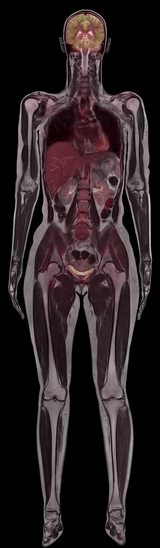

İSTANBUL – Manyetik rezonans (MR) ve pozitron emisyonu tomografisi (PET) teknolojilerini buluşturan bu yeni cihaz, ilk kez doktorlara iç organların yerlerini, nasıl çalıştıklarını ve metabolizma yapılarını aynı anda tek  görüntü içinde görme imkanı veriyor.

Siemens Sağlık Sektörü tarafından geliştirilmiş olan Siemens Biograph mMR adlı bu cihaz, Münih’teki Klinikum Rechts der Isar Üniversite Hastanesi’nde yoğun olarak kullanılıyor. Biograph mMR, normalde birbirine alternatif olan iki teknolojinin bileşiminden oluşuyor: Manyetik rezonans görüntüleme, güçlü bir manyetik alan ve elektromanyetik dalgalardan faydalanırken pozitron emisyonu tomografisinde, çekimden önce hastaya enjekte edilen düşük dozlu radyoaktif radyofarmasötik ilaçlar kullanılıyor.

Radyofarmasötik ilaçlar, vücut dokularıyla reaksiyona giriyor ve ortaya çıkan radyasyon ölçülüp nihai olarak bir görüntü şeklinde aktarılır. Bu görüntüleme tekniklerinde uygulanan fizik kurallarına göre bu iki teknolojinin birbiriyle çelişen görüntüler üretmesi gerekir ki bu da aynı anda görüntülemeyi imkânsız kılar. Ancak Siemens Biograph mMR, bu engelin üstesinden gelecek şekilde tasarlanmıştır. Söz konusu iki teknolojinin tek sistem içinde birleştirilmesinin, çok sayıda kanser türü ve demans hastalığı dâhil olmak üzere birçok hastalığın teşhisini değiştirmesi bekleniyor.